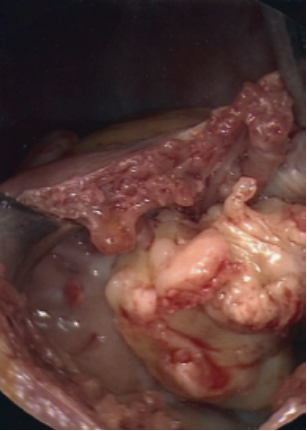

In the operating room, the patient underwent general endotracheal anesthesia. After his sternum had been divided, his right atrium and ventricle appeared distended, and there was evidence of moderate right ventricle dysfunction. On palpation of the right atrium and ventricle, the mass could be easily felt. After Heparin administration, the aorta was cannulated and there was bicaval venous cannulation. The heart was arrested and a right atriotomy was performed. The mass was stuck to the right atrium (Figure 2A and Figure 2B), tricuspid valve, and right ventricle. There was also invasion into the myocardium of the right ventricle. There was no possibility of excision of the mass in its entirety, but multiple biopsies were sent for evaluation (Figure 3). The frozen section returned as lymphoma.